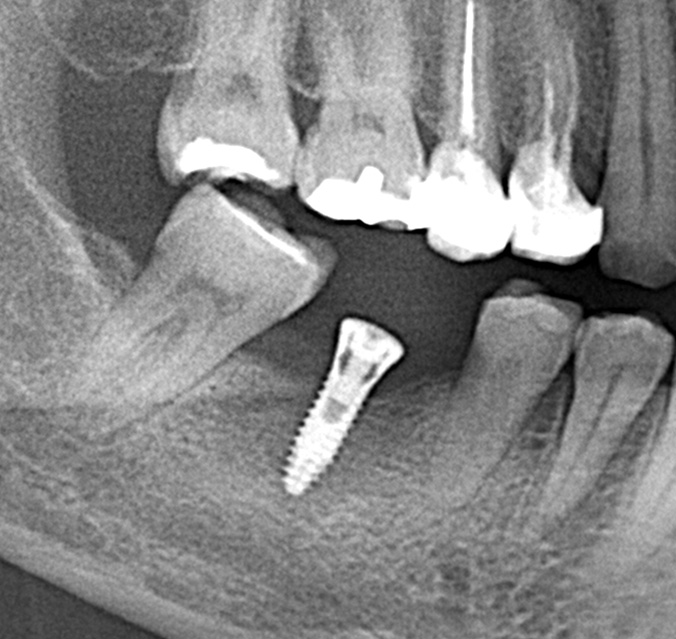

仮歯の調整期間を経て、セラミックの歯が入りました。

レントゲン画像 治療前 インプラント治療後

パノラマレントゲン写真 -

親抜歯後、歯ぐきは治癒しました。しかし、インプラント治療のためには骨が不足していました。